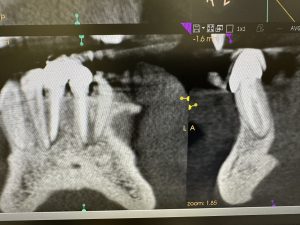

次は、歯性上顎洞炎の根管治療2カ月後

だいぶ回復💪